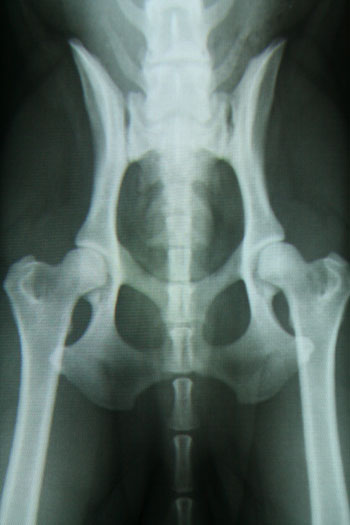

Not original - a photo from my computerscreen...